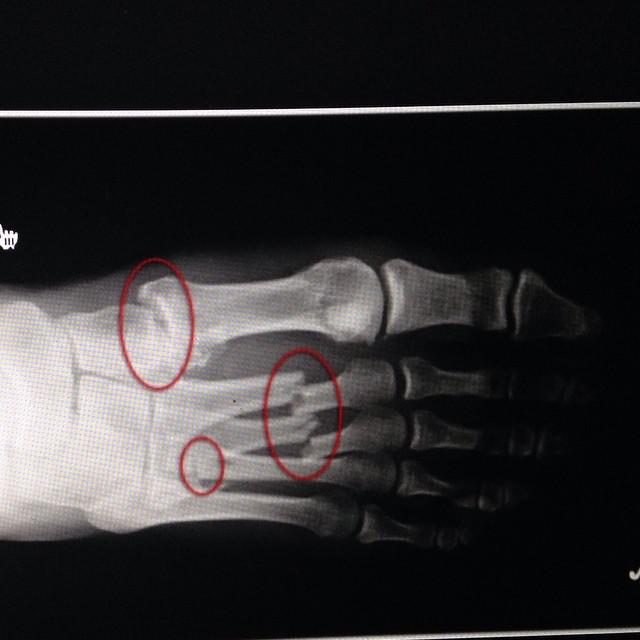

Перелом 5 плюсневой форум

Перелом 5 плюсневой форум 175 фото